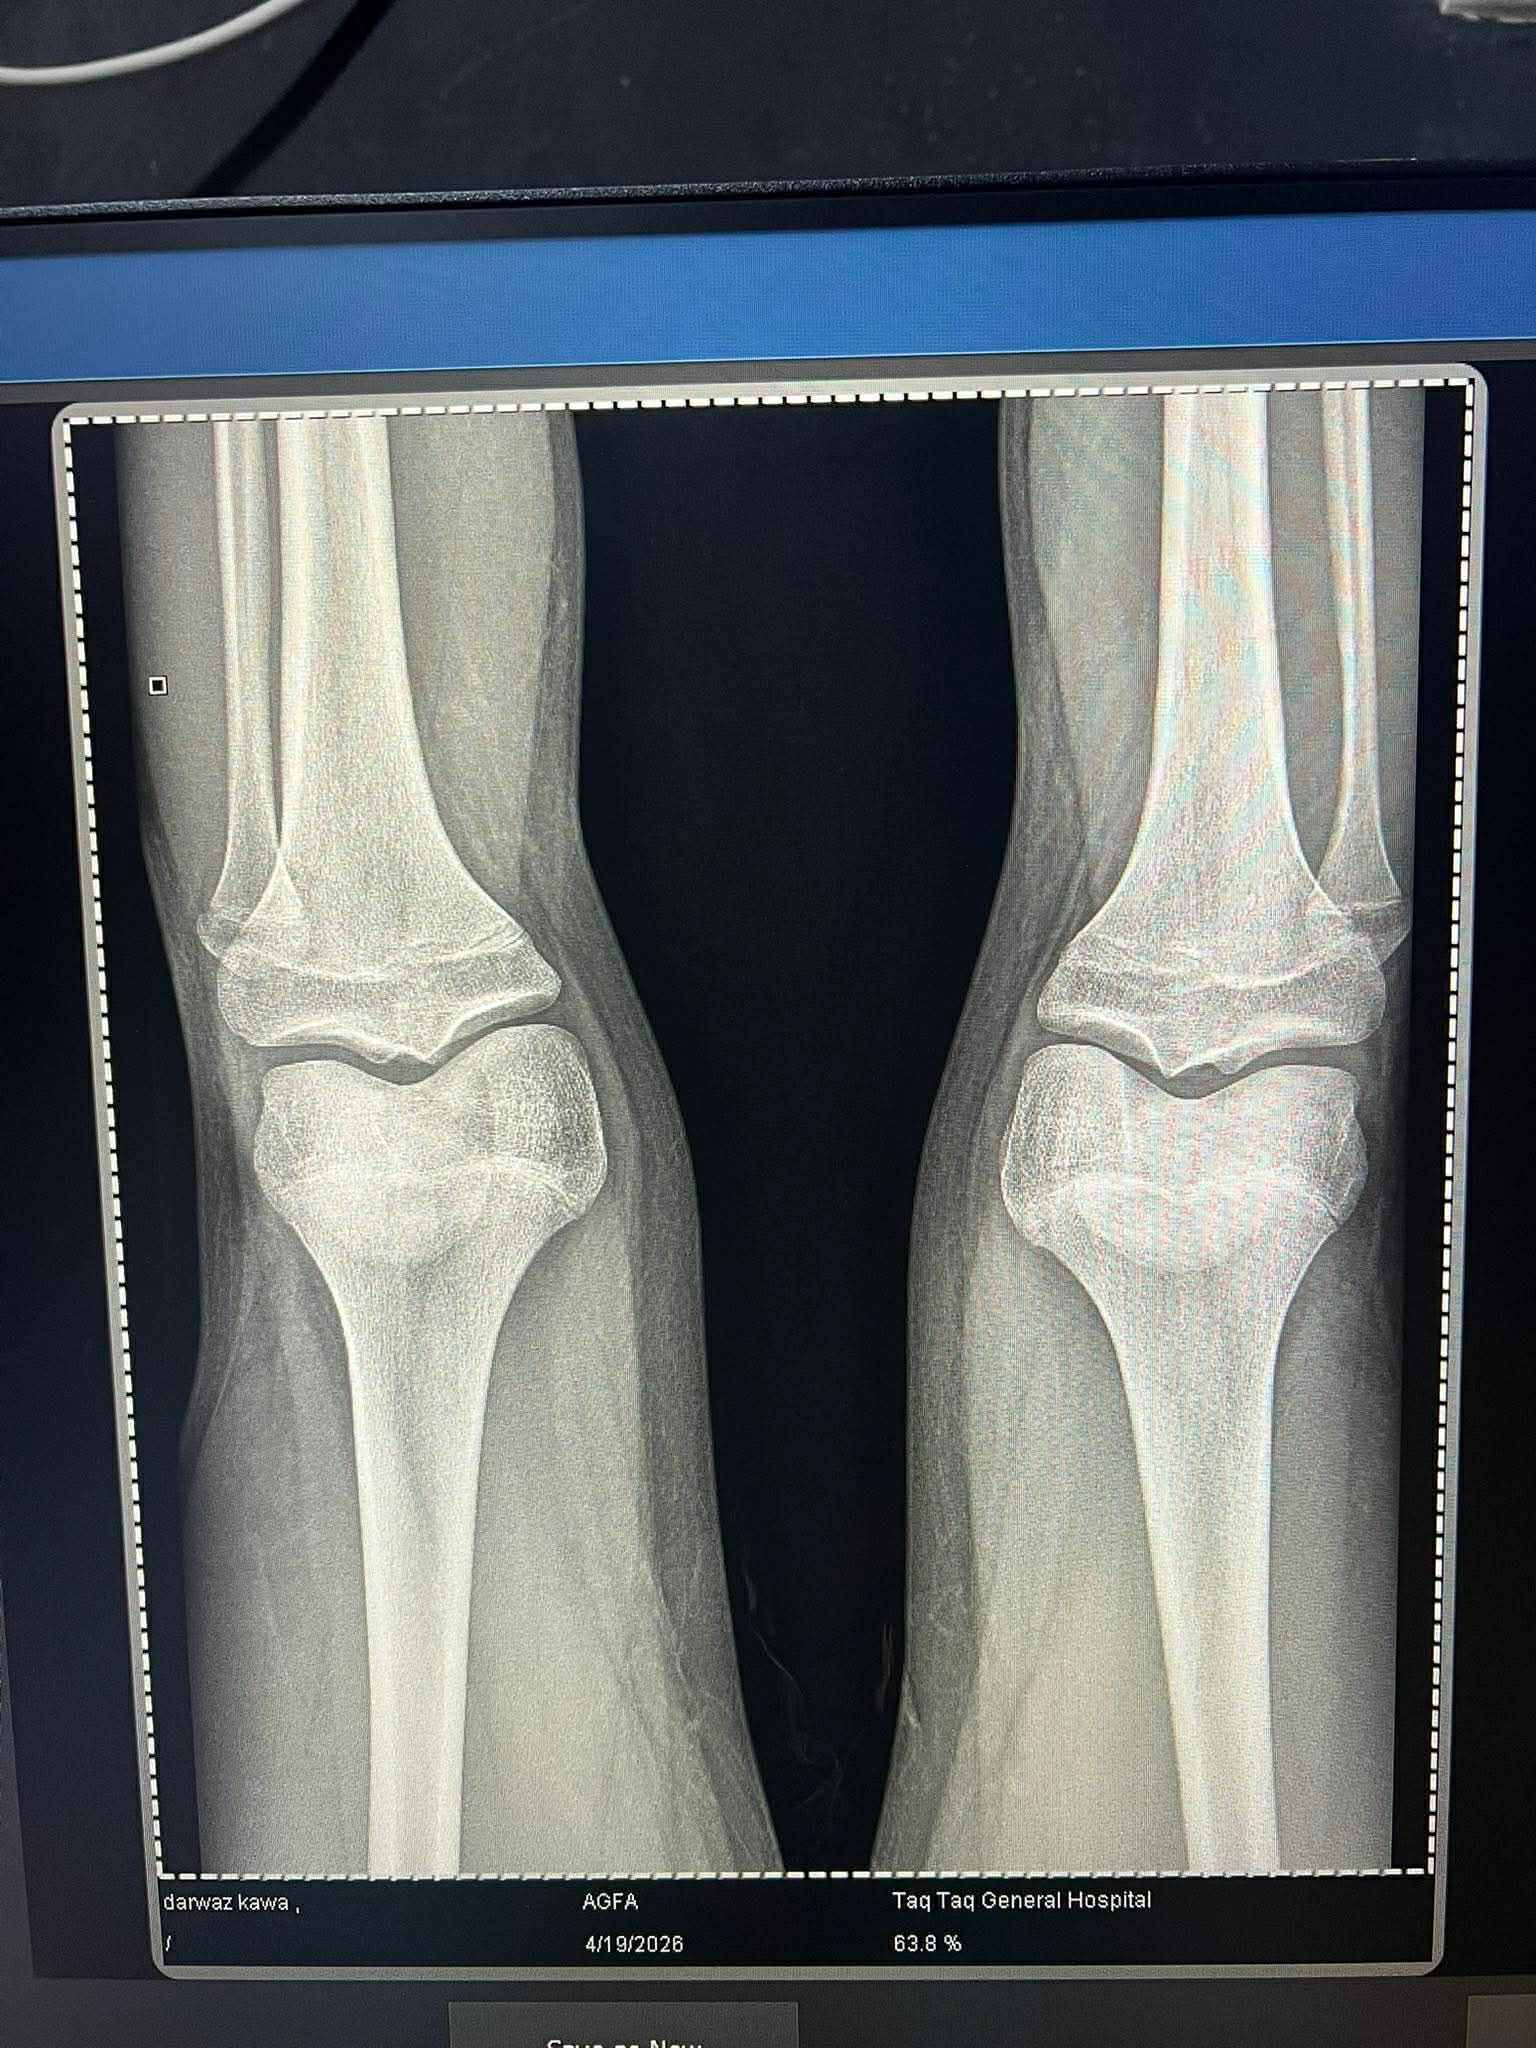

So. Igot diagnosed too late that im ghd and my plates are fusing and doc prescribed 6 ius daily and he said i wouldve prescribed u ai if u came at 14 :feelsrope::feelsrope:

IMG 2301